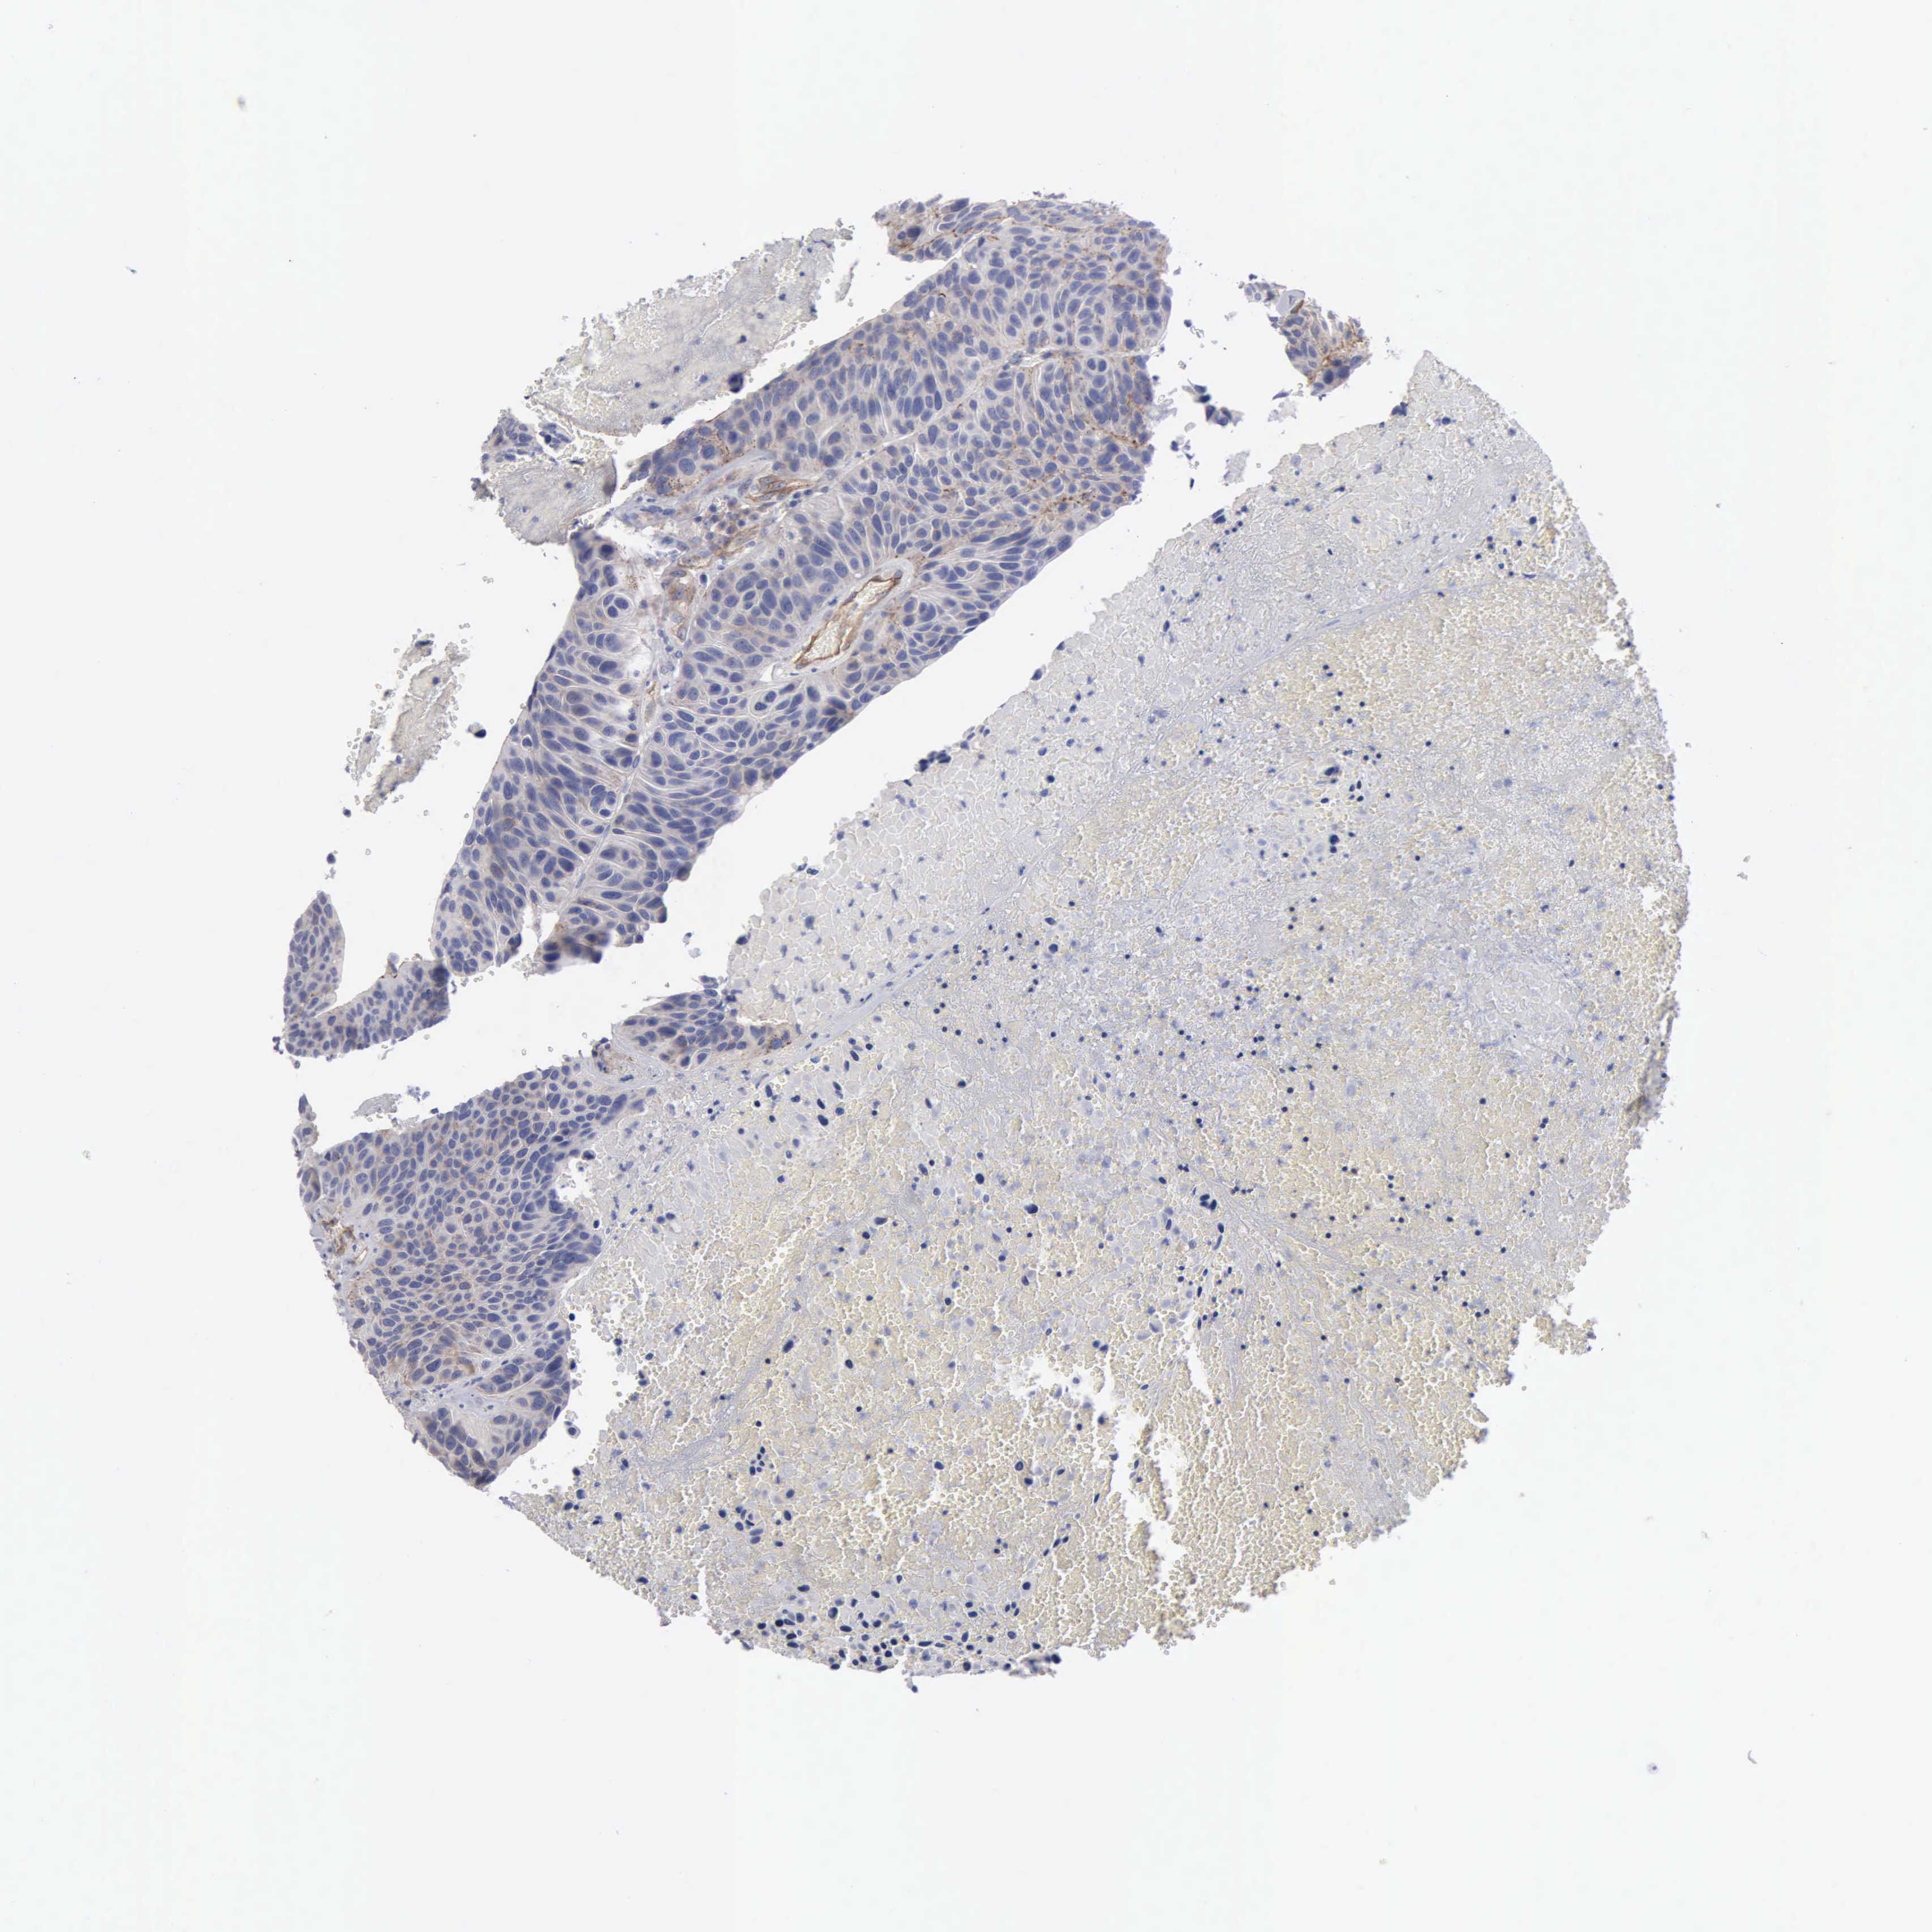

UROTHELIAL CANCER - Protein expressioni

A mouse-over function shows sample information and annotation data. Click on an image to view it in a full screen mode. Samples can be filtered based on level of antibody staining by selecting one or several of the following categories: high, medium, low and not detected. The assay and annotation is described here.

Note that samples used for immunohistochemistry by the Human Protein Atlas do not correspond to samples in the TCGA dataset.

Antibody stainingi

Antibody staining in the annotated cell types in the current human tissue is reported as not detected, low, medium, or high, based on conventional immunohistochemistry profiling in selected tissues. This score is based on the combination of the staining intensity and fraction of stained cells.

Each image is clickable and will lead to virtual microscopy that enables deeper exploration of all samples and also displays staining intensity scores, fraction scores and subcellular localization as well as patient and tissue information for each sample.

Antibody HPA000263

Antibody HPA000763

Antibody CAB037312

Staining

High

Medium

Low

Not detected

Intensity

Strong

Moderate

Weak

Negative

Quantity

>75%

75%-25%

<25%

None

Location

Nuclear

Cytoplasmic/membranous

Cytoplasmic/membranous,nuclear

Urothelial carcinoma, High grade

Urothelial carcinoma, Low grade